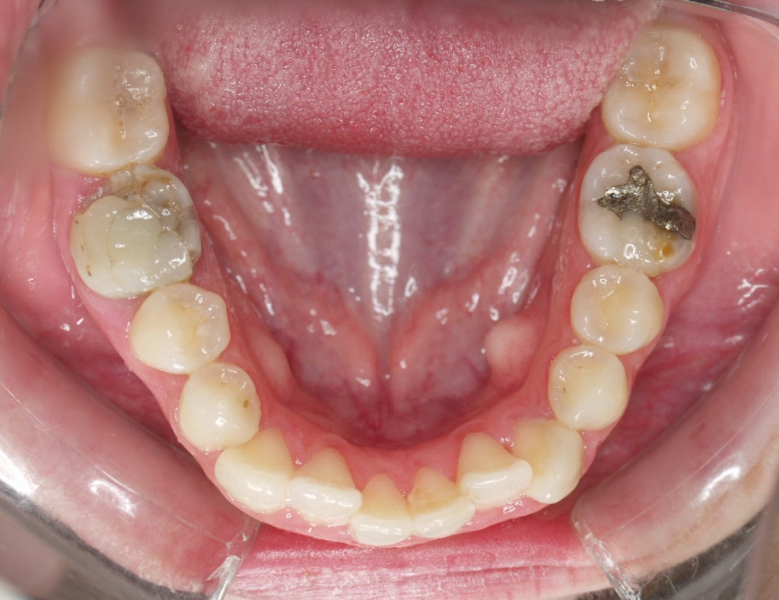

Premolar mandibular incluido + fenestración

45 incluido

Radiografía de final de tratamiento